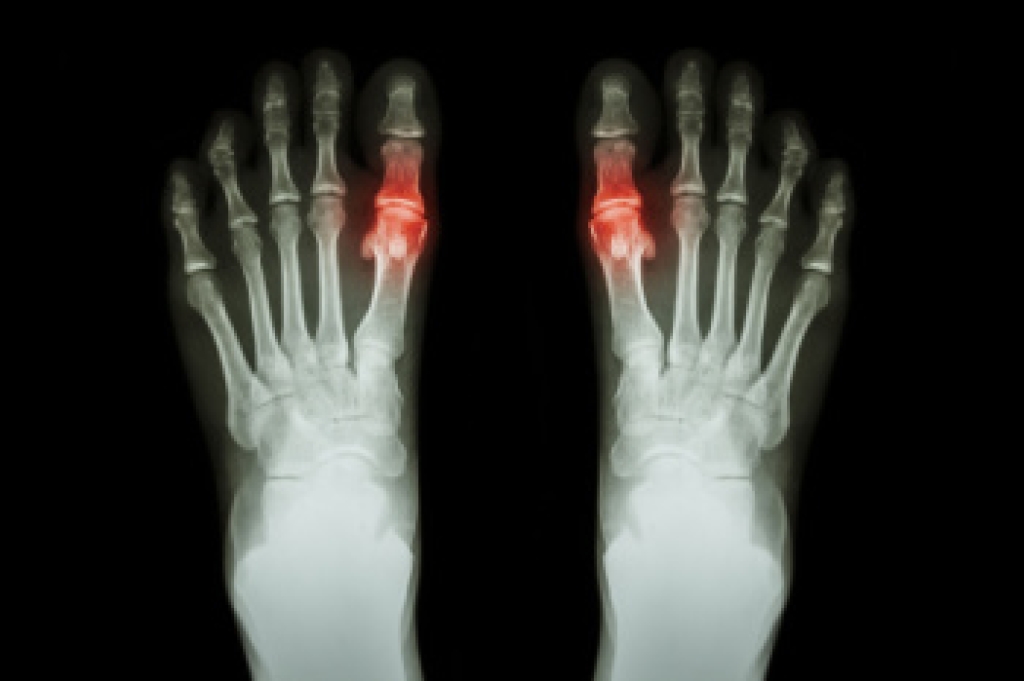

Ingrown Toenails

Ingrown toenails occur when a toenail grows sideways into the bed of the nail, causing pain, swelling, and possibly infection.